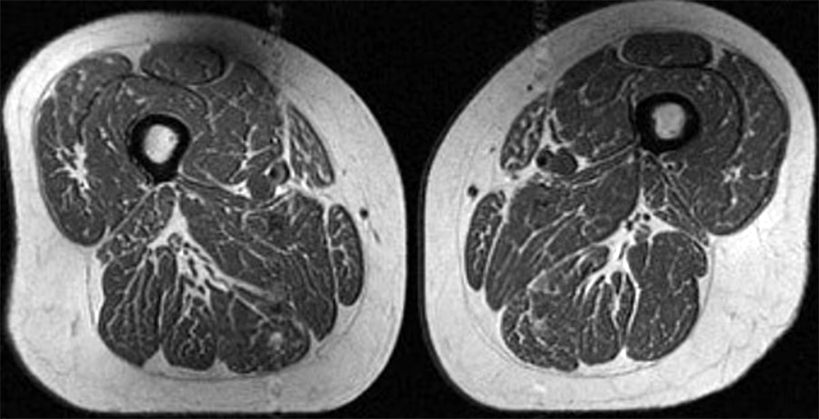

20:24:58 Yeni bir araştırma, aşırı işlenmiş gıdalar açısından zengin beslenmenin kas dokusunda yağ birikimine yol açabileceğini gösteriyor. Bu durum, görüntü olarak ince yağ damarlarıyla kaplı bir bifteği andırıyor. Ancak bu bir yemek değil; yıllık kalorisinin %87’sini ultra işlenmiş gıdalardan alan 62 yaşındaki bir kadının uyluk kasına ait MR görüntüsü… Kaliforniya Üniversitesi San Francisco’daki araştırma ekibinden Dr. Zehra Akkaya’ya göre bu kişinin beslenmesi ağırlıklı olarak paketli tahıllar, çikolatalar ve şekerli içeceklerden oluşuyordu. Kas liflerinin arasında biriken bu yağ dokusu, ciddi sağlık sorunlarının habercisi olabilir. Araştırma, özellikle diz osteoartriti riski taşıyan bireylerde ultra işlenmiş gıdaların kas kalitesi üzerindeki etkisini inceliyor. Ultra işlenmiş gıdalar; obezite, kanser, kalp hastalıkları, tip 2 diyabet ve depresyon gibi birçok kronik hastalıkla ilişkilendiriliyor. Ayrıca yaşam süresini kısaltabileceğine dair bulgular da mevcut. ABD verilerine göre yetişkinlerin günlük kalorilerinin %50’den fazlası, çocukların ise %62’si bu tür gıdalardan geliyor. Çalışmada incelenen başka bir katılımcının (61 yaş) kaslarında da yağlanma görüldü; ancak bu kişi kalorilerinin yalnızca %29’unu ultra işlenmiş gıdalardan alıyordu ve yağlanma daha sınırlıydı. Araştırmacılara göre en dikkat çekici nokta, henüz diz osteoartriti belirtisi göstermeyen bireylerde bile kas kalitesinin bozulmaya başlamış olması. Kas içine yerleşen yağ hücreleri, kas liflerinin yenilenmesini engelleyerek kasları zayıflatır. Zayıf kaslar ise dünya genelinde yüz milyonlarca insanı etkileyen diz osteoartritinin önemli nedenlerinden biridir. Bu hastalık artık sadece yaşlılarda değil, daha genç yaş gruplarında da sık görülüyor; bunun başlıca nedenlerinden biri artan obezite. Uyluk kasları diz stabilitesi için kritik öneme sahiptir. Bu kaslardaki güç kaybı, özellikle fazla kilolu bireylerde ekleme binen yükü artırır. Uzmanlara göre kas içi yağlanma genellikle sadece tek bir bölgeyle sınırlı değildir; vücudun diğer kaslarında da benzer değişiklikler görülebilir. Bu durum, kasların genel olarak zayıfladığını ve ileride sağlık sorunları riskinin arttığını gösterir. Radiology dergisinde yayımlanan çalışma, diz osteoartriti belirtisi olmayan 615 kişinin MR görüntülerini analiz etti. Ortalama yaş 60, ortalama vücut kitle indeksi ise 27 idi. Sonuçlar net: Araştırma doğrudan nedensellik kanıtlamasa da güçlü bir ilişki ortaya koyuyor. İyi haber ise şu: egzersiz ve sağlıklı beslenmeyle kas kalitesi yeniden iyileştirilebilir. Uzmanlar, eklemleri korumak için düşük etkili egzersizleri öneriyor. Özellikle: Eliptik bisiklet Kuvvet antrenmanı Bacak kaslarını hedefleyen egzersizler Beslenmede ise: Evde hazırlanmış, doğal gıdalar tercih edilmeli Yeterli protein alınmalı İşlenmiş atıştırmalıklar ve şekerli içecekler azaltılmalı Pratik öneriler: Etiket okuyun, daha az işlenmiş ürünleri seçin. Tam tahıllar, sebzeler ve baklagillere ağırlık verin. Şekerli içecekler yerine su tüketin. Fast-food yerine daha az işlenmiş seçenekler sunan yerleri tercih edin.